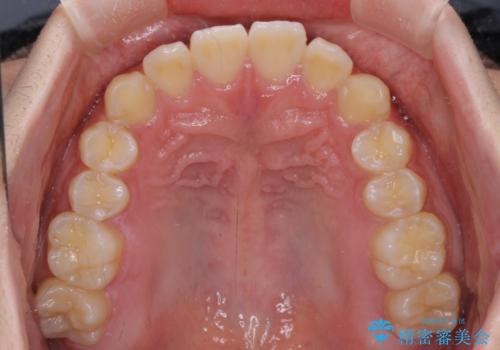

- 前方に傾斜した前歯を気にして来院された患者様です。

強く食いしばってしまう癖があり、下顎前歯に押し出されて上顎前歯が前方へ斜めに突き出している状態でした。

IPR(歯と歯の間を削る)を多用して、インビザラインにて矯正治療を行うこととしました。

口元を引っ込めるためのゴムかけを頑張っていただき、満足のいく上顎前歯の傾斜へ改善することができました。